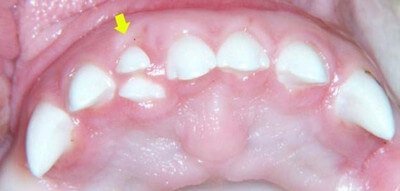

Picture 1: Supernumerary teeth behind the central incisors.

Image Source: supernumeraryteeth.com